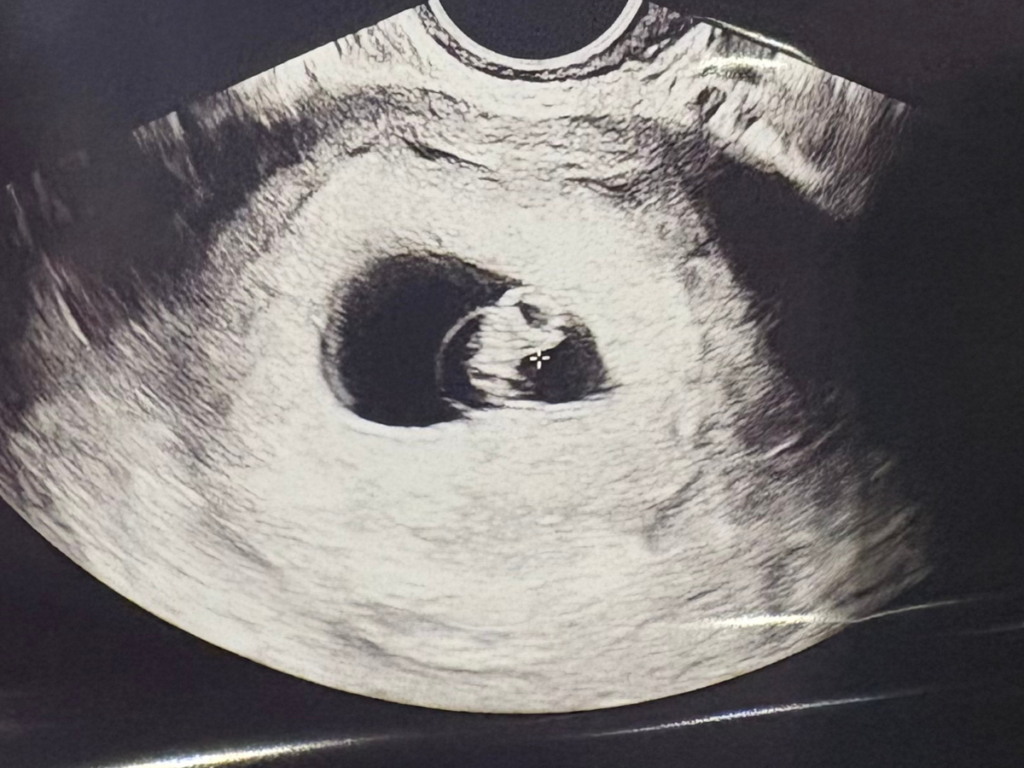

Black and white ultrasound image showing a small embryo inside a gestational sac, centered within the image, as commonly seen in early pregnancy scans, including those following endometriosis IVF treatments.